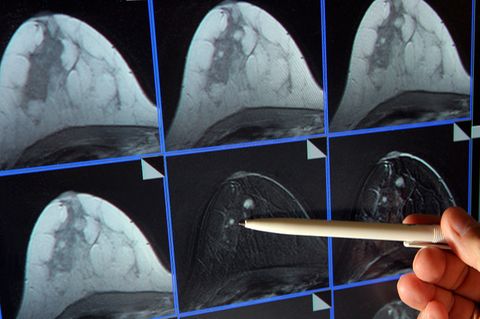

Auch hier gilt: Krebs ist nicht gleich Krebs. Es wird nie das eine Heilmittel für Krebs geben, sondern verschiedene Therapieformen für verschiedene Krebsarten. Beispiel Brustkrebs: Früher wurde Brustkrebs immer gleich behandelt. Inzwischen kann man durch Analysen eine Vielzahl von Krebsarten in der Brust unterscheiden und je nachdem, welche Form vorliegt, unterscheidet sich auch die Therapie. Auch weiß man heute, dass manche Frauen mit Brustkrebs von einer Chemotherapie gar nicht profitieren. Andere dagegen sehr. Das kommt ganz auf die Analyse des jeweiligen Tumors an. Aber DAS eine Mittel gegen alle Krebsformen wird es nie geben.